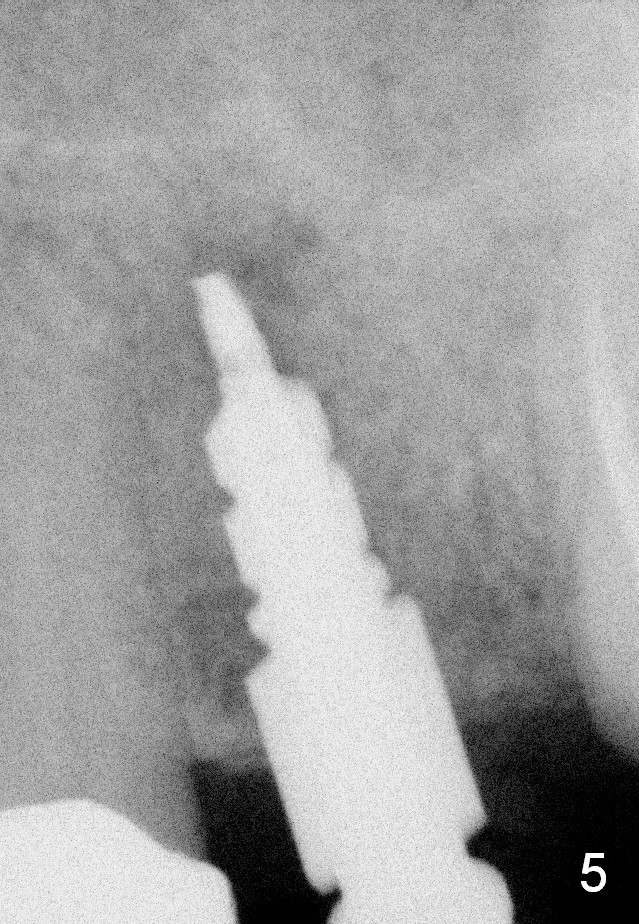

A 45-year-old lady is nervous about dental treatment. The missing tooth #13 was replaced by a 3-unit bridge. The latter is sectioned because the posterior abutment has caries. PA in Fig.1 is taken when root canal therapy and build up are finished. Fig.2 shows the wide edentulous area with a single-unit crown being tried in for #14. Osteotomy is initiated with the crown in place without cementation, since it is easy to determine the mesiodistal position (Fig.3 red lines). Without the crown in place, osteotomy tends to be distal. In this case, the osteotomy is later attempted to be moved distally with Lindamann bur and deepened to 14 mm from the gingival margin (Fig.4). A 2.5 mm reamer is being used at 50 RPM to increase osteotomy with difficulty. Drills have to used at high RPM instead (Fig.5 4x14 mm). A 4.5x14 mm tissue-level implant is placed with insertion torque >60 Ncm (Fig.6 I); a 4x3 mm abutment (A) is placed immediately for an immediate provisional. Fig.7 is taken 7 days postop to show the gingival recipient site formed by the provisional. The patient is so afraid of X-ray that the next one is taken 1.5 years post cementation (Fig.8). It appears that dense bone bundle forms between the crest and the 1st implant thread (adaptation functional change, arrowheads). The bone density continues to increase 2 years 8 months post cementation (Fig.9 *, 10); the bone has grown into the area between the 1st 2 threads (arrow).